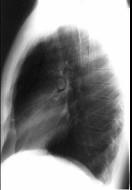

问题 在哮喘急性发作的病程中患者出现颈部皮下气肿,胸片见图。说明此患者有下列哪一种并发症存在 ( )

选项 A.气胸 B.纵隔气肿 C.间质性肺气肿 D.肺囊肿 E.肺大疱

答案 B